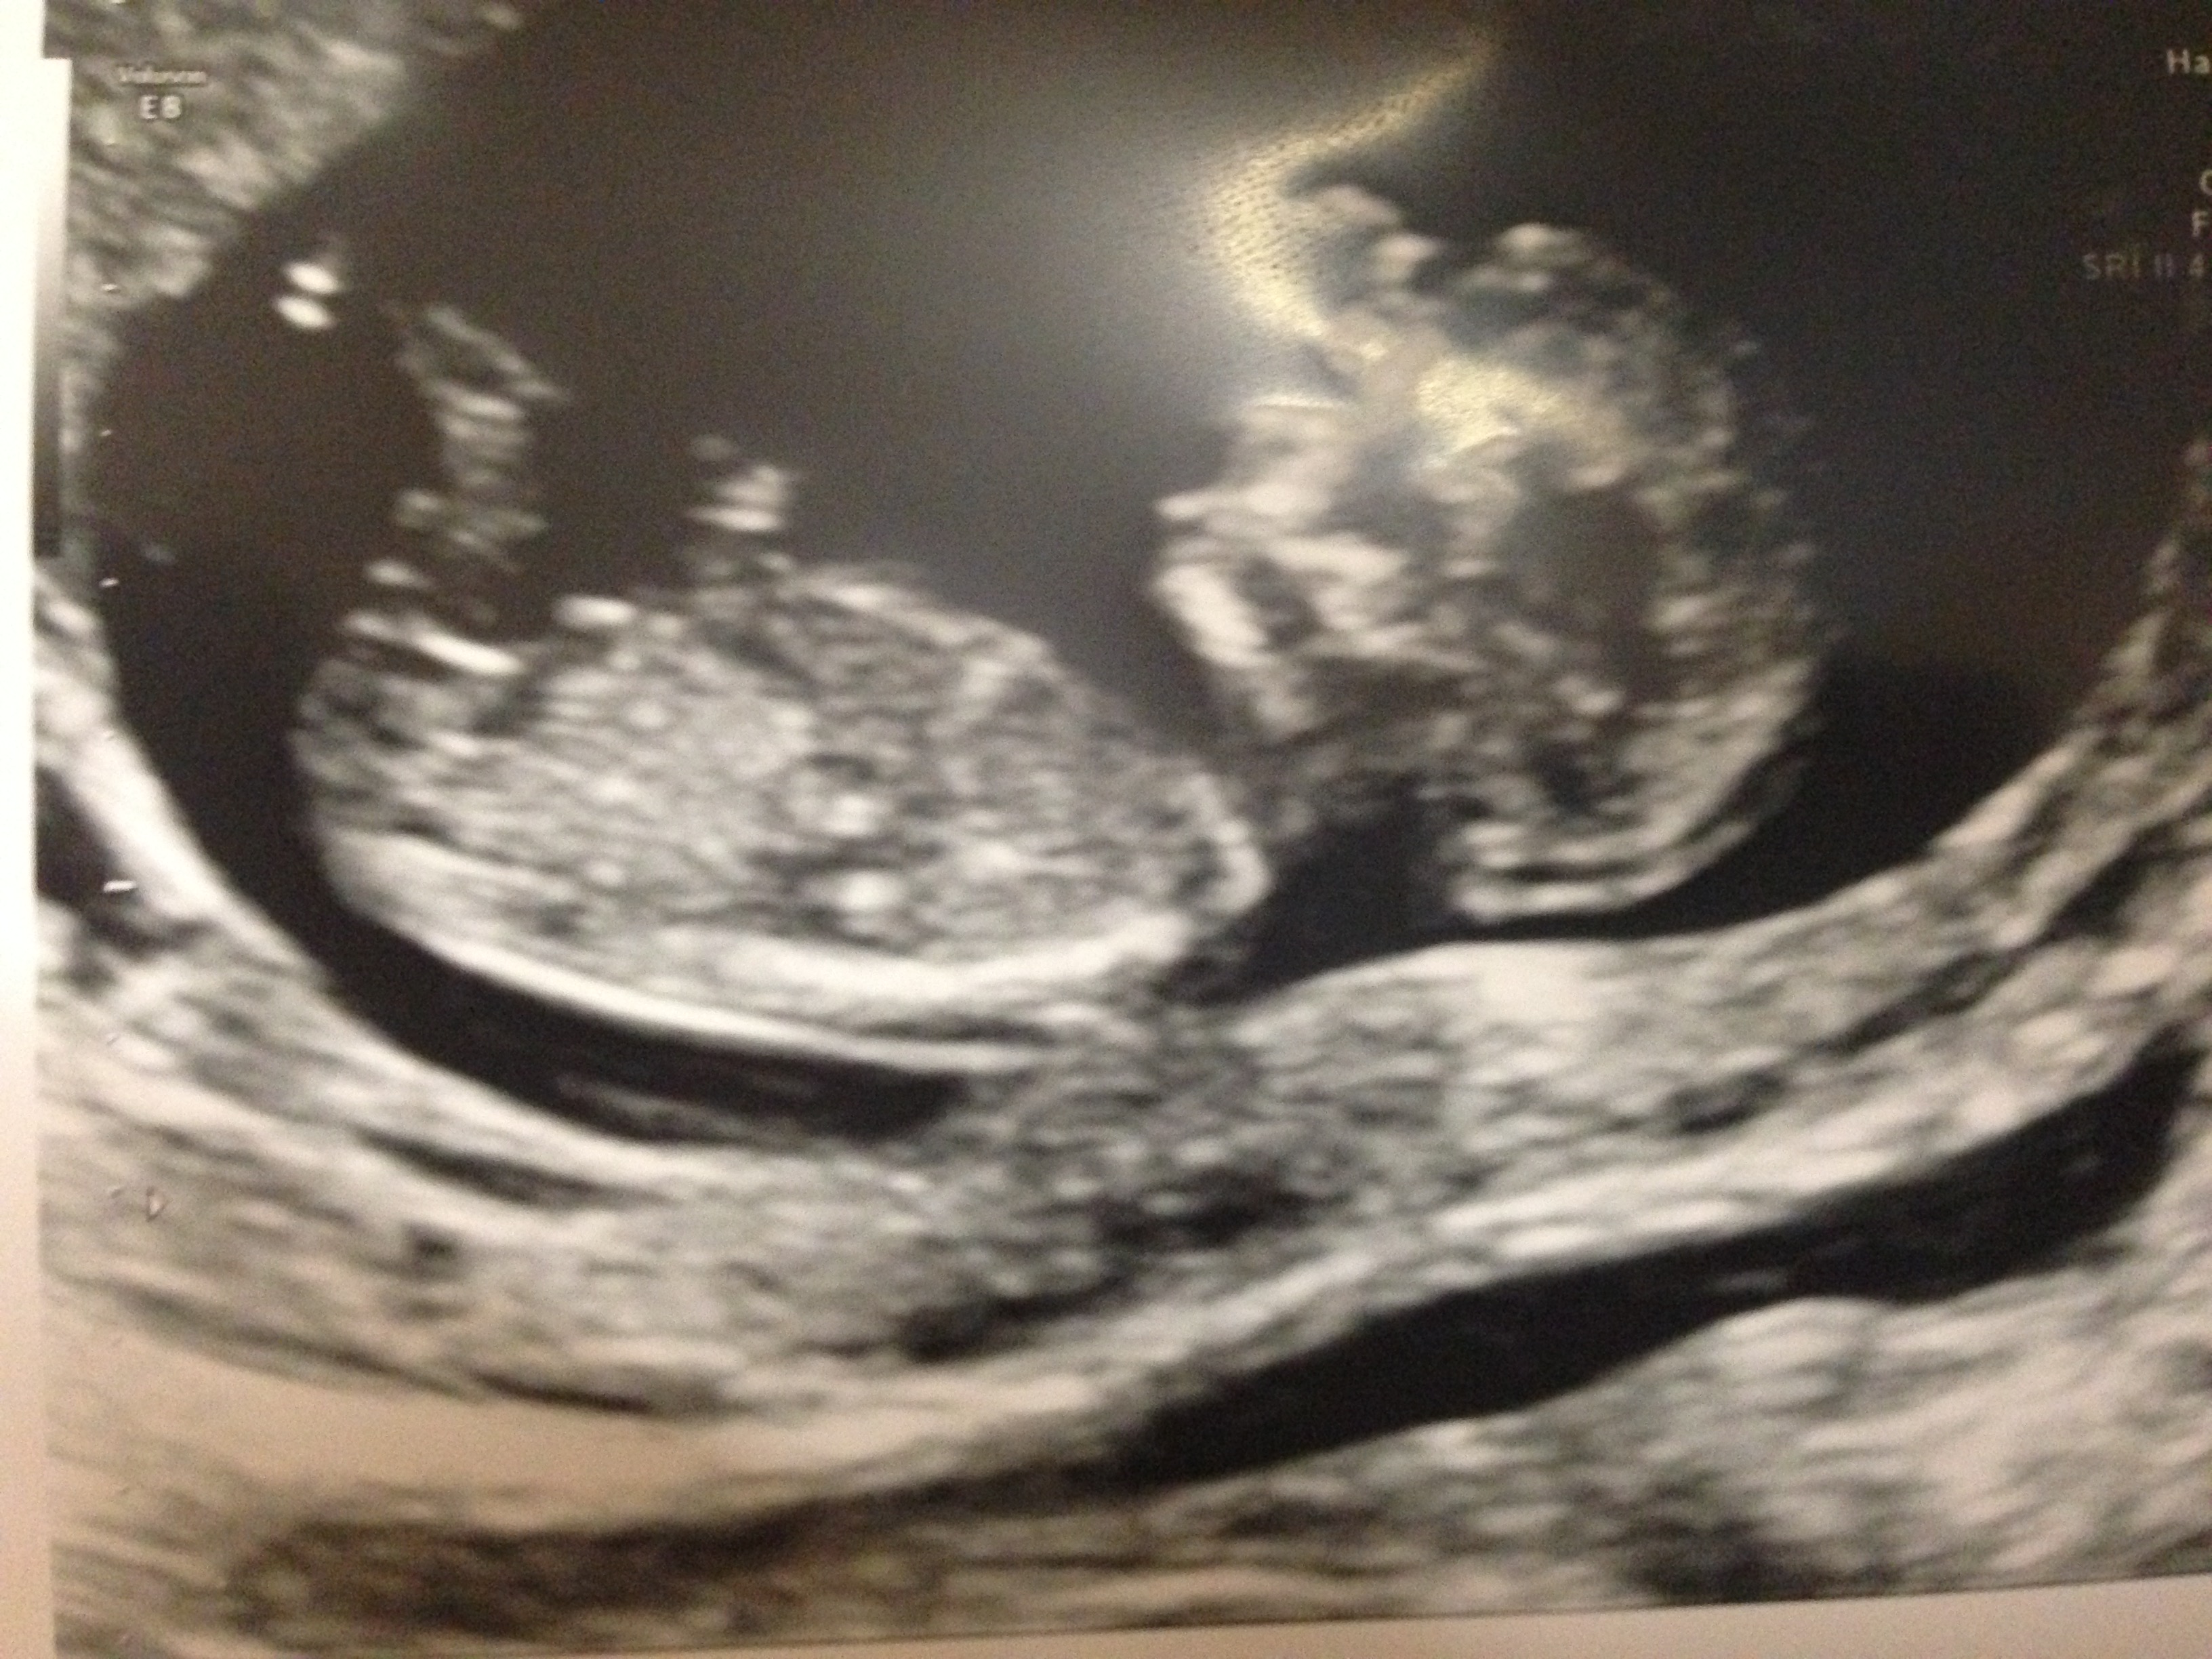

Tricky but guessing boy. This could go either way :)

boy from me, I see some stacking there.

Girl guess due to the angle

Girly Sent from my GT-I9305T using Tapatalk